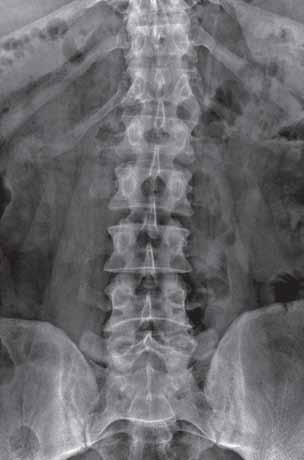

Zmiany proliferacyjne, w tym syndesmofity i entezofity (patrz: podstawowe definicje), są charakterystyczne dla spondyloartropatii zapalnych.

Osteofity, obok podchrzęstnej sklerotyzacji, są cechą charakterystyczną ChZS. W chorobach reumatycznych dochodzi do powstania wtórnych zmian zwyrodnieniowych w postaci osteofitów brzeżnych, zlokalizowanych na krawędziach powierzchni stawowych. W ich etiopatogenezie podkreśla się znaczenie m.in czynnika zapalnego.

Odczyny okostnowe w chorobach reumatycznych są wynikiem procesu zapalnego toczącego się w tkance kostnej. Najczęściej są widoczne wzdłuż trzonów kości śródręcza, śródstopia oraz trzonów paliczków. Występują w przebiegu MIZS, ŁZS i MŁZS, ReZS, CRMO i SAPHO. Niekiedy powodują wyrównanie wklęsłego zarysu paliczków, aż do znacznego ich pogrubienia i zniekształcenia (tzw. paliczki czopkowe), co może

być jedynym objawem MIZS. W RZS mogą być obserwowane we wczesnym okresie choroby wzdłuż dalszych odcinków trzonów kości podudzi.